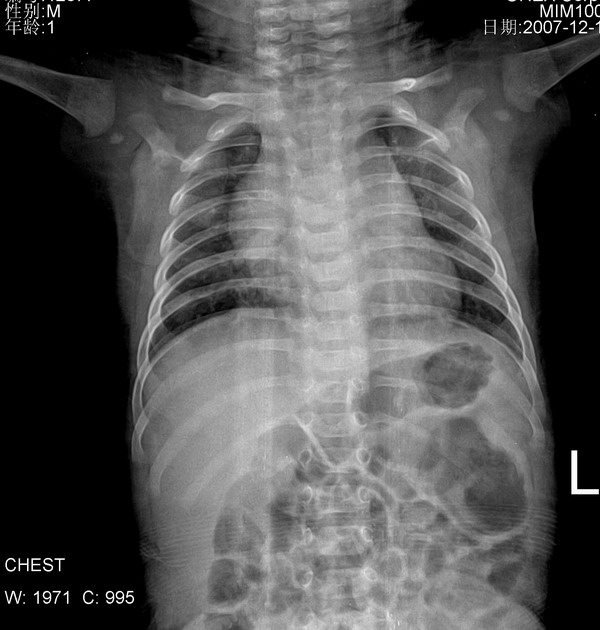

小儿肺1 仰卧前后位, 男110天,咳嗽2天,夜间尤甚,心脏听诊断无异常, 老师们给个意见!纵隔?

胸腺增大

小儿新影正常,有气肿改变纹理重,小儿肺炎.

支气管肺炎

加照侧位片,,先考虑胸腺增大.

先考虑胸腺增大.心肺膈未见明显异常。

纵隔增宽是胸腺影,心脏建议彩超

正常胸腺

正常。仰卧位纵隔心影都增宽

小儿正常胸腺似胸腺肥大。

考虑胸腺增大。建议心超检查。

支持胸腺肥大所致。

不太像增大的胸腺,支气管肺炎诊断请结合临床病史。

支气管肺炎----纹理增重,双下肺可见小斑状增密影。

有心缘改变首先考虑为胸腺所致,考虑支气管肺炎